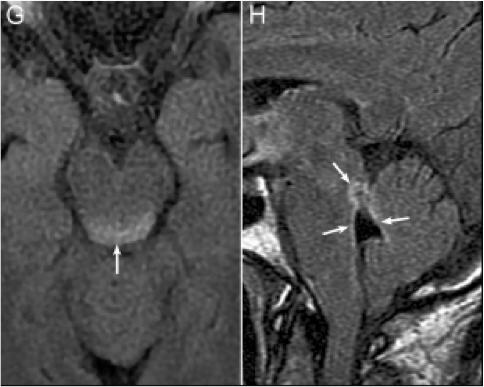

3. NMOSD 脑干MRI:四脑室周围,分布集中